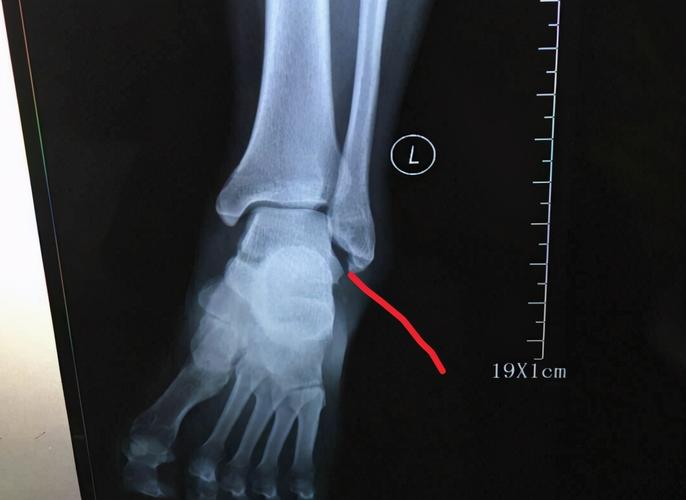

外踝扭伤了,肯定要拍个踝关节正侧位片,看看有没有腓骨下端的骨折

右脚踝扭伤,腓骨骨折,关节移位.请看x光片,谢谢.